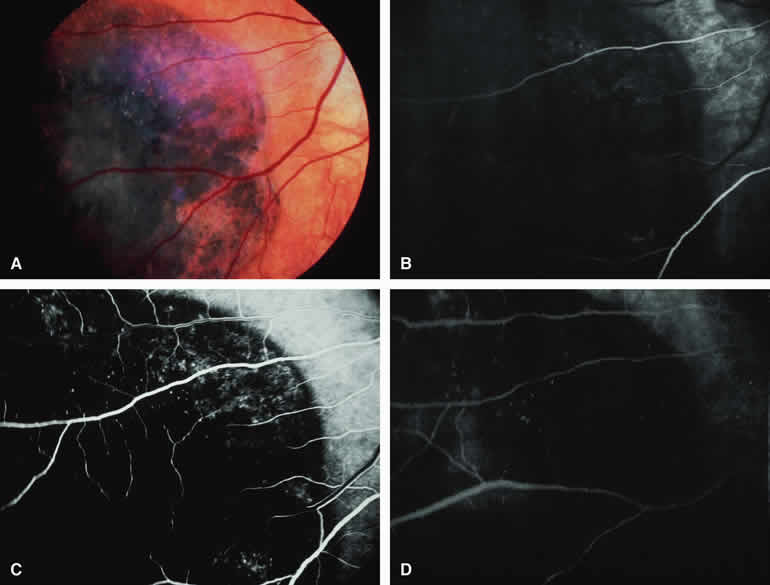

Choroidal Melanoma with Retinal Invasion

Occasional choroidal melanomas develop darkly melanotic patches of retinal invasion on their surface. These patches appear as homogeneous dark brown velvety lesions obscuring the examiner's view of the large retinal vessels (Fig. 15A). Fluorescein angiography of such a lesion (see Fig. 15B, C, and D) shows the darkly pigmented mass to be completely nonfluorescent throughout the entire study. The retinal blood vessels at the margins of the lesion are often abnormal and leaky, as might be expected on the basis of the associated retinal invasion.